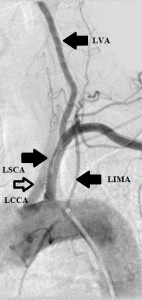

Key: LVA, left vertebral artery; LSCA, left subclavian artery; LCCA, left common carotid artery; LIMA, left internal mammry artery

The 4 images you see above were recorded by me during primary stenting of irregular atherosclerotic stenosis of the left subclavian artery in a 54-year-old hispanic female who was referred to my interventional radiology clinic for management of the stenosis. She had presented to her primary care physician with symptoms of hindbrain ischemia upon using her left upper limb and earlier workup confirmed left subclavian arterial stenosis. The 2 top images illustrate the character and severity of her disease, the first image in the bottom row shows the process of balloon-expandable stenting of the disease, while the 2nd image in the bottom row reveals complete elimination of the stenosis and reappearance of the left vertebral and internal mammary arteires, which were invisible on the pre-intervention angiograms reflecting the severity of the stenosis.